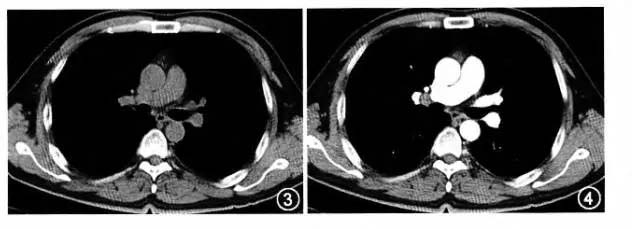

CT意为计算机断层摄影术是用X线束对人体层面进行扫描,根据人体组织吸收X线强度的差异由计算机重建生成二维断面灰阶图像,简单理解就是加强版的X线片

ct是应用x线成像的,所以对人体有辐射危害。因为ct检查比较快,并且对含气脏器的检查,有其独特的优势,所以应用比较广泛。

目前ct检查主要应用于胸部,腹部,头颅,四肢骨关节,复杂骨折,骨肿瘤、骨结核等,可以检查出并诊断人类的大多数疾病。

相对于X线片更加清晰,可以看到不同断层的骨组织和软组织的情况,但是四种检查中CT的辐射最大,不建议经常使用。